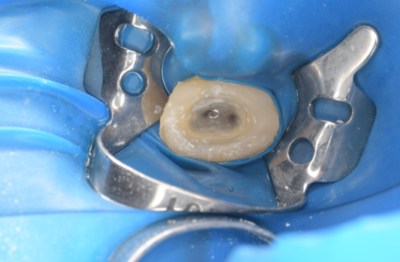

抜歯1ヶ月後

移植手術後

右上6抜歯1ヶ月後、移植手術を行った。

右下8を抜歯し右上6部に移植、縫合糸で固定した。

移植手術後、治癒に異常を認めなかったため、移植2週間後に根管治療を行った。